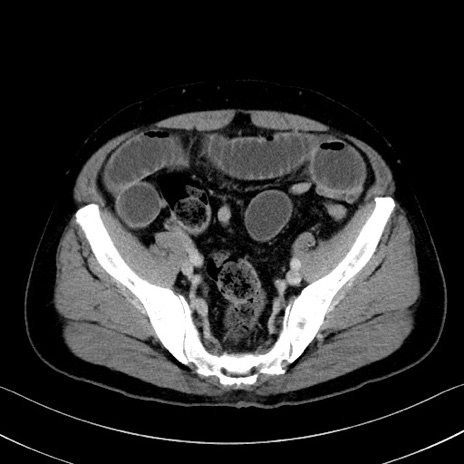

症例35(横断像)

【症例】70歳代 男性

【主訴】腹部膨満、嘔吐

【現病歴】昨日より腹部膨満感出現。本日増悪し、仙痛出現。嘔吐あり、受診。

【既往歴】糖尿病、胆摘後

【身体所見】BP 149/80mmHg、HR 74/min、BT 35.9℃、腹部:膨満、軟、圧痛なし。腸雑音減弱あり。上腹部正中切開瘢痕あり。

【データ】WBC 13500、CRP 1.72